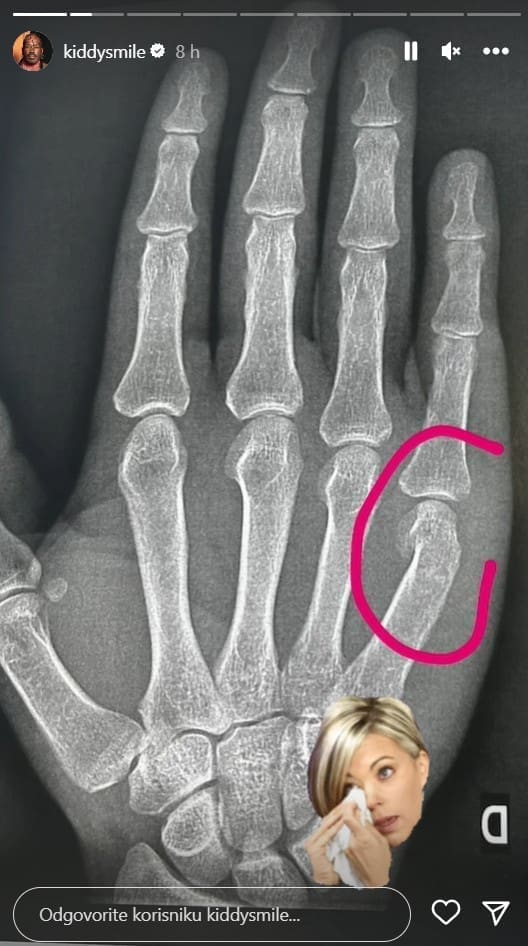

- Ne mogu vjerovati da se moram oglašavati o ovome, ali mislim da je bitno da se zna što se dogodilo. Osjećaju su mi pomiješani, a ruka slomljena - započeo je, prenose 24sata.

- Počeo se derati na mene te me udario. Pokušao sam ga zaustaviti, ali me udario još jednom. Tada sam izgubio kontrolu i srušio sam ga na pod. Došlo je osiguranje te ga smirilo. Bio sam jako uzrujan jer sam bio na lijepom festivalu i super se provodio sa svojim prijateljem. Ne mogu vjerovati da sam udaren zato što sam homoseksualac. Primio sam dva udarca jer sam razmišljao o tome u kakvu ću se poziciju dovesti kao izvođač ako udarim nekoga na festivalu, a pri tome sam druge rase i 'queer' - dodao je.

- Na ovom sam festivalu od prvog njegovog održavanja i neću dopustit da to utječe na moju sliku o njemu te na moju sliku o Hrvatskoj. Vratit ću se i bolje me nemojte zezati i dirati mi ruke jer su mi one potrebne za posao - zaključio je.